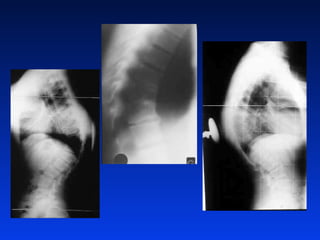

CA LAO CS NGÖÏC

Vieâm thaân soáng ñóa ñeâm do lao

CA LAO CSNGÖÏC

Vieâm thaân soángñóa ñeâm do lao